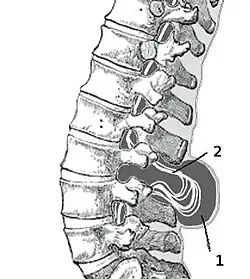

Clasificare

(1) Sac extern cu lichid cefalorahidian(LCR)

(2) Măduva spinării herniată și prinsă între vertebre

Mielomeningocel

Mielomeningocelul este forma cea mai frecventă și severă de spină bifidă, cu complicațiile cele mai grave.[5] Mielomeningocelul apare atunci când meningele și măduva spinării ies prin spațiul intervertebral(herniază) sub forma unui sac. Spina bifidă cu mieloschizis este forma cea mai gravă a mielomeningocelului. La acest tip de afecțiune zona afectată este reprezentată de o masă de țesut nervos fără membrană de protecție, ceea ce expune bebelușii la infecții periculoase cum ar fi meningita.[6]

Deoarece măduva spinării prin creștere exercită tracțiune asupra măduvei, circulația lichidului cerebrospinal este întreruptă motiv pentru care cei mai mulți copii care se nasc cu acest tip de spină bifidă prezintă și hidrocefalie (o acumulare de fluid în creier și în jurul creierului).

Ca rezultat al mielomeningocelului poate să apară paralizie sau pierderea simțurilor sub nivelul afecțiunii, probleme de mers, deformarea bazinului, picioarelor sau pierderea tonusului muscular.